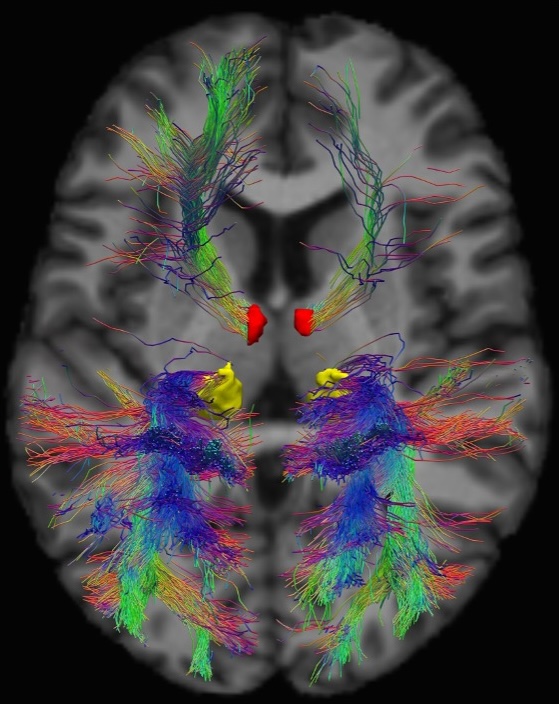

The Integrative Thalamus:

Computation, Connectivity and Disease